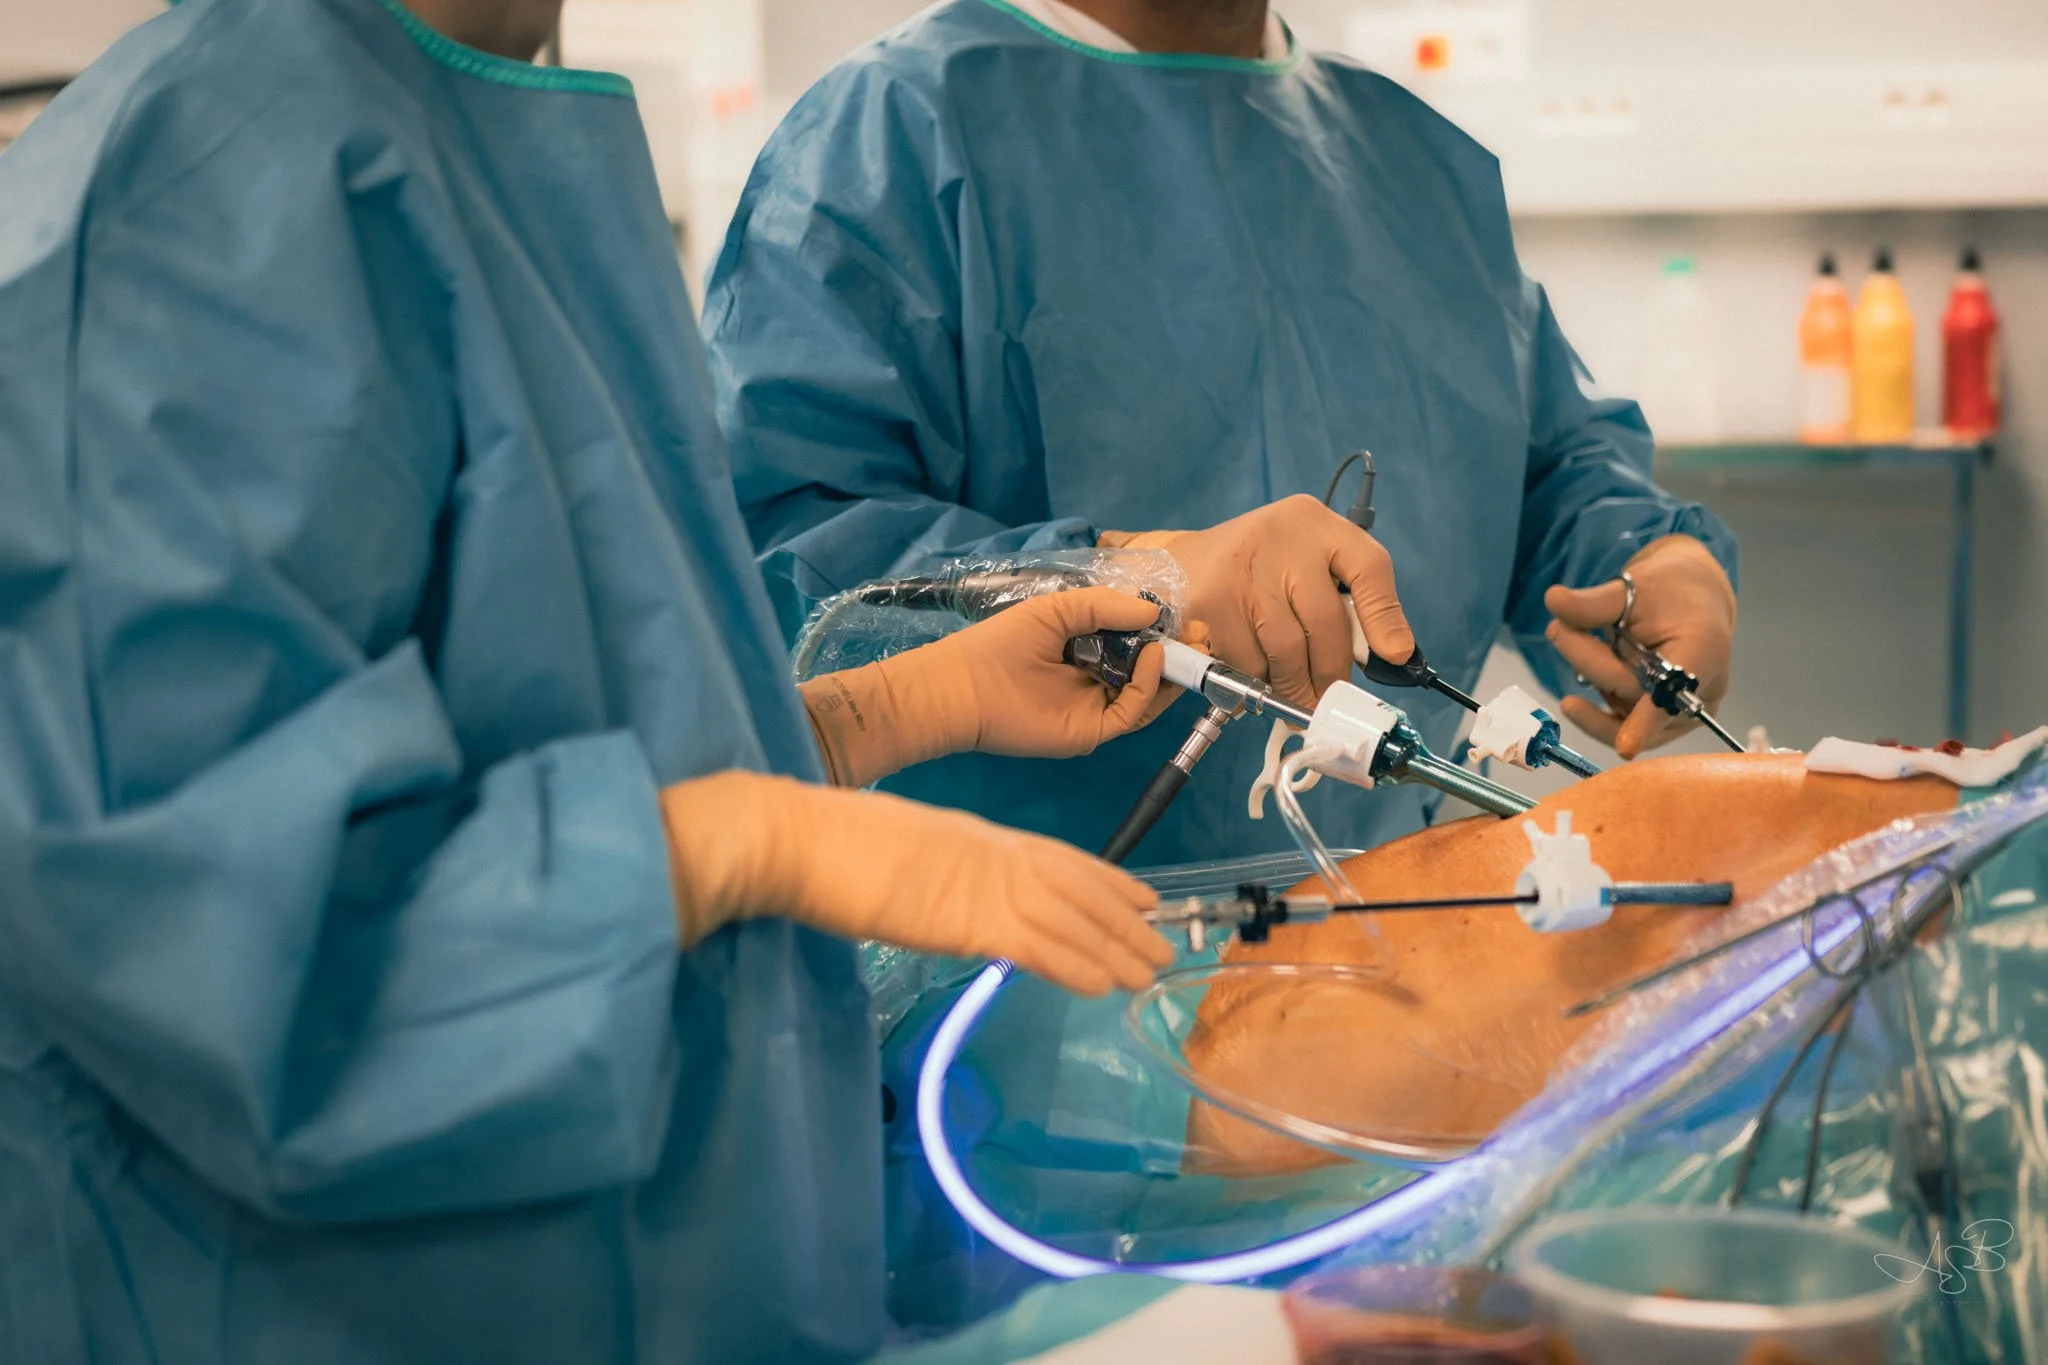

Partie 2 (bas de page) : La chirurgie des Femmes